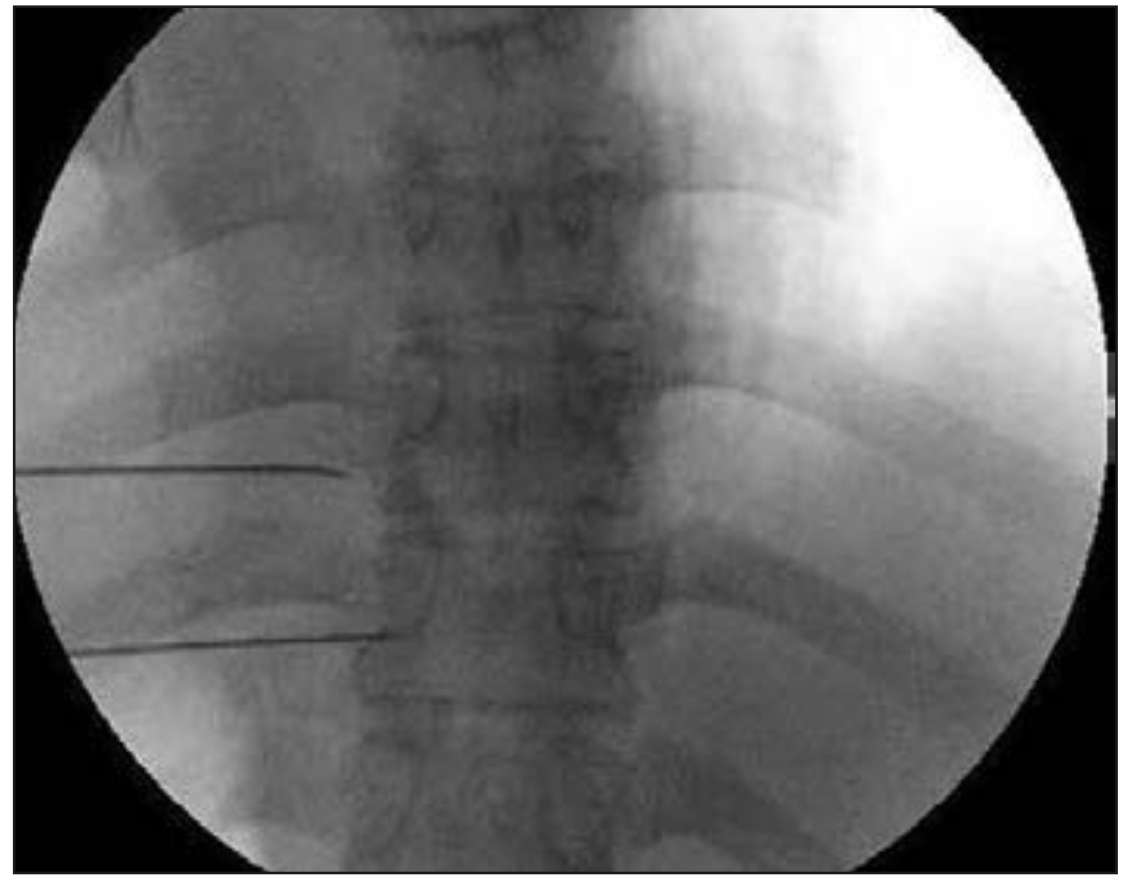

Oh et al (21) publicaron una serie de 100 pacientes con dolor de pared torácica secundario a cáncer, donde realizaron radiofrecuencia termal (80-90°C) a los nervios espinales torácicos, usando cánulas de radiofrecuencia no traumáticas para obtener parestesias a estimulación sensitiva (50 Hz, 0,5 V) bajo fluoroscopia.

Figura 5. Visión fluoroscópica anteroposterior donde se observan cánulas de radiofrecuencia en espacio paravertebral (21).

Previo al procedimiento, el dolor evaluado vía Escala Visual Análoga (EVA) era de 7 (rango 3–10), disminuyendo posteriormente al procedimiento a EVA 4 (0–9) a la semana y al mes después (ambos P <0,001), y manteniéndose en EVA 4 (1-8) a los 6 meses después del procedimiento (P <0.001).